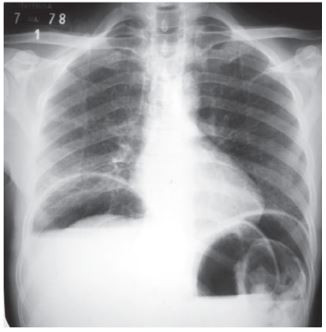

Homem, 41a, relata que há 1 hora apresentou dor súbita de forte intensidade, tipo pontada, no epigástrio, que irradiou para todo abdome. Refere náusea. Nega febre ou sintomas respiratórios. Exame físico: PA=128x76mmHg, FC= 102bmp, FR= 16irpm, oximetria de pulso (ar ambiente)= 99%, corado, hidratado e acianótico; Abdome: plano, tenso, doloroso à digitopercussão e à palpação superficial e profunda, com descompressão brusca dolorosa presente. Radiograma simples de abdome ortostático: